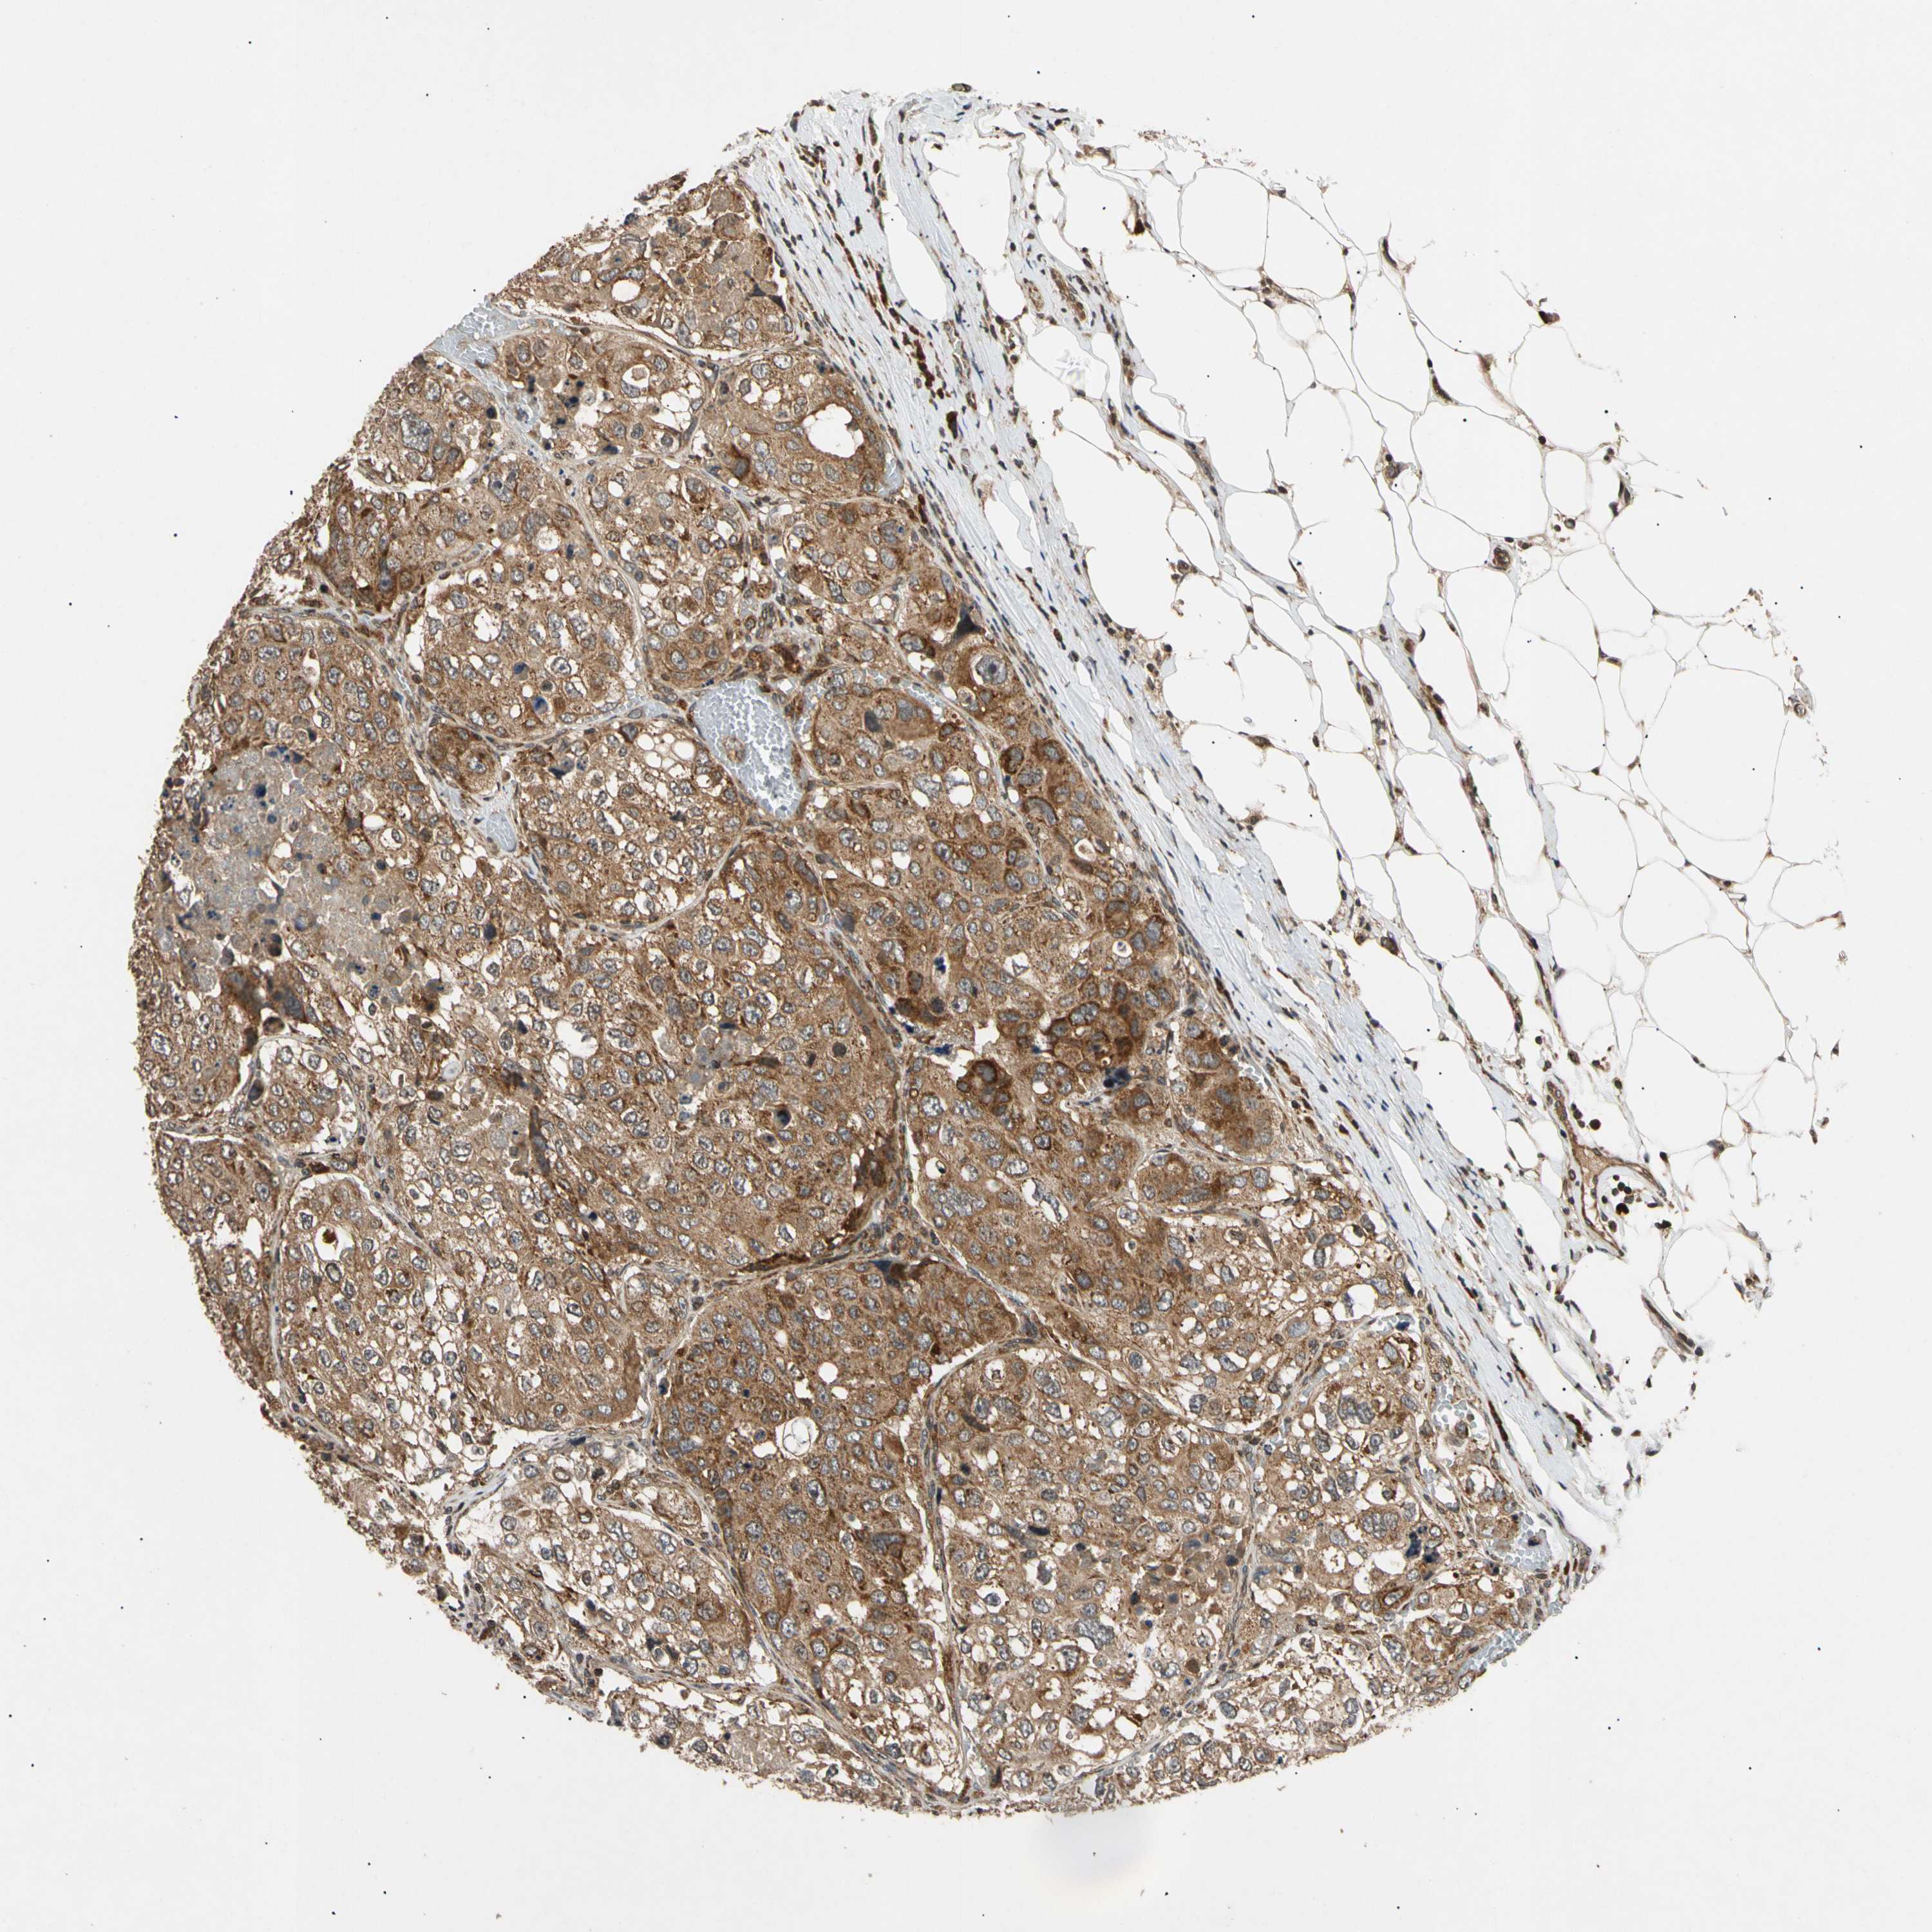

UROTHELIAL CANCER - Protein expressioni

A mouse-over function shows sample information and annotation data. Click on an image to view it in a full screen mode. Samples can be filtered based on level of antibody staining by selecting one or several of the following categories: high, medium, low and not detected. The assay and annotation is described here.

Note that samples used for immunohistochemistry by the Human Protein Atlas do not correspond to samples in the TCGA dataset.

Antibody stainingi

Antibody staining in the annotated cell types in the current human tissue is reported as not detected, low, medium, or high, based on conventional immunohistochemistry profiling in selected tissues. This score is based on the combination of the staining intensity and fraction of stained cells.

Each image is clickable and will lead to virtual microscopy that enables deeper exploration of all samples and also displays staining intensity scores, fraction scores and subcellular localization as well as patient and tissue information for each sample.

Antibody HPA006083

Antibody HPA007830

Staining

High

Medium

Low

Not detected

Intensity

Strong

Moderate

Weak

Negative

Quantity

>75%

75%-25%

<25%

None

Location

Nuclear

Cytoplasmic/membranous

Cytoplasmic/membranous,nuclear

Urothelial carcinoma, High grade

Urothelial carcinoma, Low grade